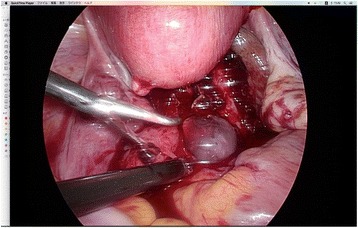

Transvaginal ultrasound was performed and a gestational sac (GS) could not be located in the uterus, but there was a GS containing a fetus consistent with 8 weeks 6 days of gestation (crown rump length: 18.8 mm) near the pouch of Douglas. (Fig. 1) An EP was diagnosed, and the patient was transported to another hospital because our clinic does not have an operating room suitable for laparoscopy. The laparoscopic diagnosis was an unruptured AEP of the pouch of Douglas. (Fig. 2). The gestational tissue was removed by forceps, and electrocauterization was used for hemostasis under laparoscopic surgery. The serum β-HCG was less than 0.5 IU/L 33 days after surgery.

Fig. 2.

Laparoscopic view of gestational sac near Douglas cavum